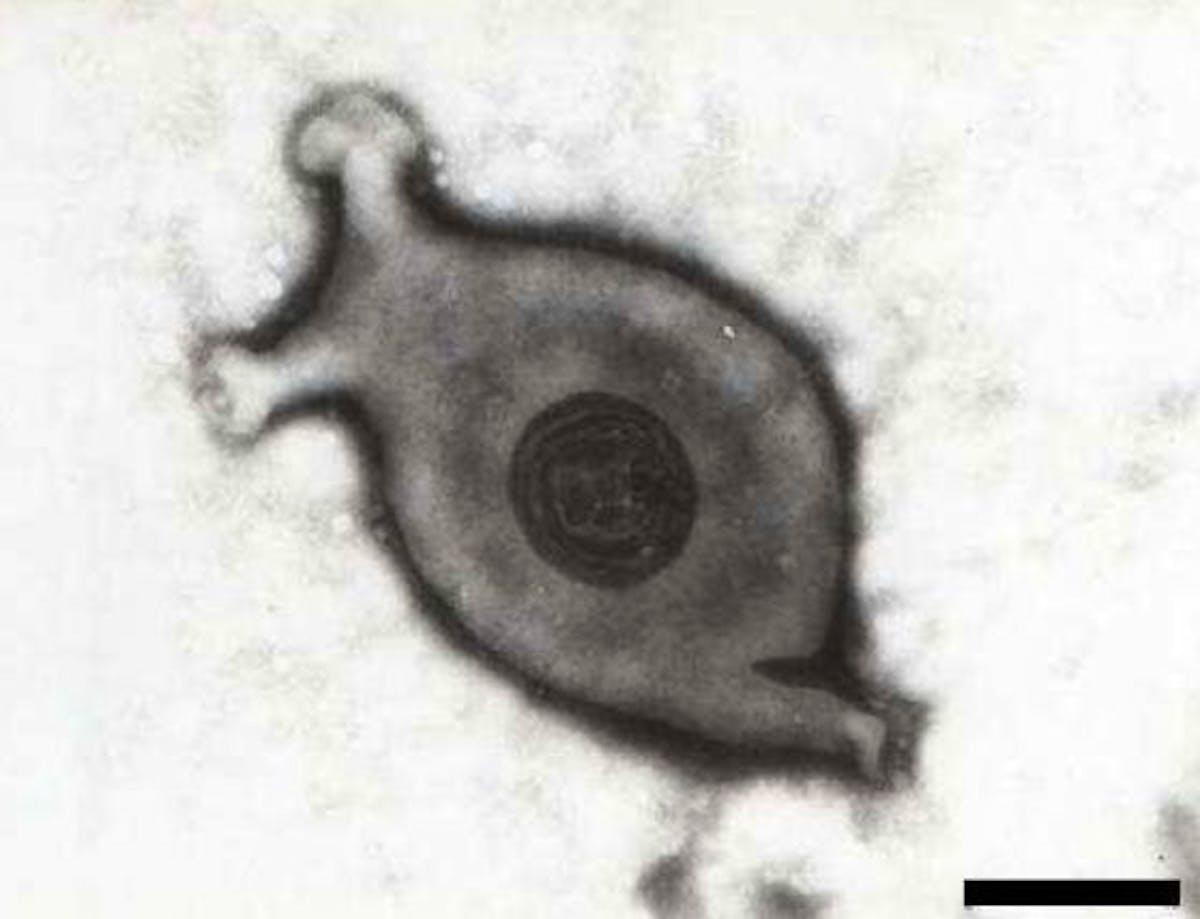

Микоплазмоз - серьезное бактериальное заболевание кур, требующее внимания от птицеводов и ветеринаров. В этой коллекции иллюстраций вы найдете подробные изображения симптомов, патогенеза и методов борьбы с этой инфекцией. Художники-медики мастерски передают клиническую картину: вялость птиц, воспаление слизистых, проблемы с дыханием и снижение яйценоскости. Особенно впечатляют микроскопические изображения: бактерии Mycoplasma gallisepticum под увеличением, их структура и способы распространения. Коллекция включает профилактические меры - вакцинацию, биобезопасность, правильное содержание. Не менее интересны экономические аспекты: как болезнь влияет на продуктивность стада, затраты на лечение. Арты выполнены в различных форматах - от диаграмм до инфографики. Эти иллюстрации помогают птицеводам вовремя распознать проблему и принять меры.